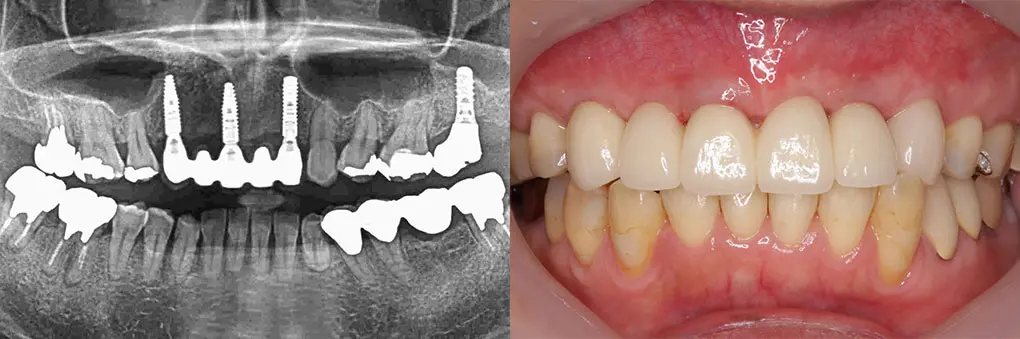

【症例2】右下欠損部をインプラントで治療したい(70代男性)

| 主訴・背景 | 入れ歯をしたくないのでインプラントで固定式にしたい |

|---|---|

| 診断・治療前の状態 | 右下第二大臼歯を抜歯して2カ月 |

| 治療方針・計画 | 右下第一第二大臼歯に2本インプラントを埋入し、第二大臼歯に骨造成術を併用 |

| 手術・処置内容 | ⚫︎ 治療部位46,47 インプラント3本 ⚫︎ 第二大臼歯に骨造成術を併用治療 ⚫︎ ストローマン社 TL ⚫︎ 上部構造 ジルコニアセラミッククラウン |

| 治療期間・回数 | 治療期間2カ月/4回通院 |

| 費用・料金(自費診療の場合) | 700,000円 |

| リスク・注意点・術後ケア | セラミック破折、インプラント周囲炎、インプラントと天然歯間の食片圧入、定期検診 |

| 治療後の状態・経過写真 | 現在、術後2年経過良好 「よく咬めると満足しています」 |

| まとめ・院からのコメント | 特に臼歯部インプラントと天然歯の隙間が拡大し、食片圧入が起こる可能性があります。その時は補綴物再製で対応します。 |